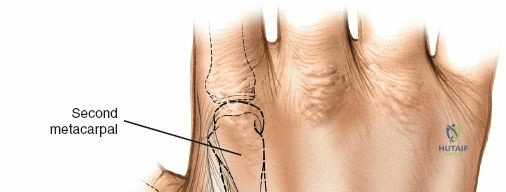

Wrist and Metacarpal Safe Zones

For spanning wrist fixators, distal pins are placed in the second metacarpal. The safe zone is the dorsoradial aspect of the second metacarpal base and shaft. The first dorsal interosseous muscle and extensor tendons must be respected. The radial artery courses proximally in the anatomic snuffbox and must be avoided during basal metacarpal pin insertion.

Metacarpal Pin Placement

1. Make two 1 cm incisions over the dorsoradial aspect of the second metacarpal.

2. Dissect bluntly, protecting the dorsal sensory branches of the radial nerve and the extensor tendons.

3. Place the tissue sleeve at a 45-degree angle to the dorsal and lateral planes to maximize purchase in the metacarpal shaft.

4. Pre-drill and insert two 3.0 mm pins.

Construct Assembly and Reduction

Connect the metacarpal pins and the radius pins with a multi-pin clamp or individual pin-to-bar clamps. Apply longitudinal traction to utilize ligamentotaxis to restore radial length and radial inclination. Volar tilt is often restored by translating the distal fragment or applying a slight volar directed force before tightening the frame. Confirm reduction with PA and lateral fluoroscopy.